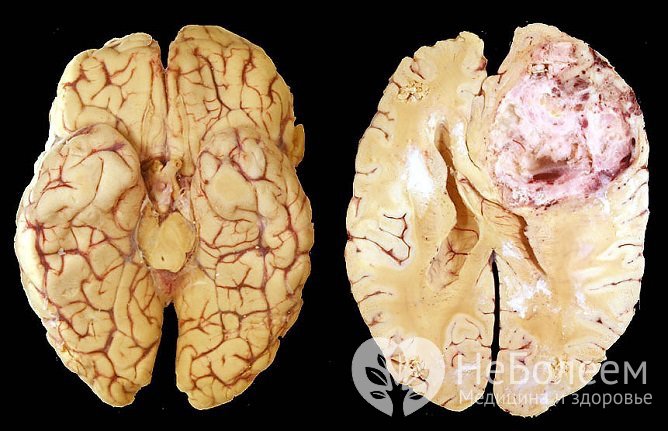

Мультиформная глиобластома, внешний видПо степени злокачественности выделяются:

При высокой степени злокачественности 50% пациентов погибают в течение первого года с момента постановки диагноза, лишь 25% живут более двух лет.

Прогноз в большинстве случаев неблагоприятный. Ввиду невозможности полного удаления опухоли заболевание быстро рецидивирует.

После хирургического удаления глиом I степени злокачественности при условии минимальных послеоперационных неврологических осложнений свыше пяти лет живут около 80% пациентов.